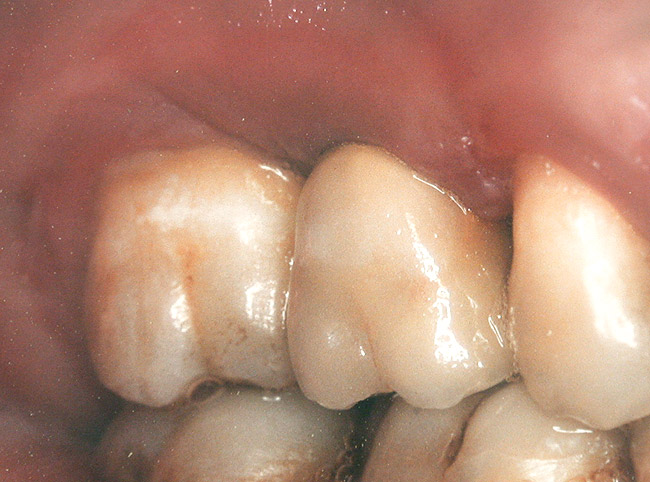

At the time of surgery, the tooth was extracted without harvesting any mucosal flap because the implant site was prepared by means of a pilot drill bur (Figure 13) and alternating osteotomes (Figure 14A and Figure 14B). The implant was positioned and showed primary stability. The implant was loaded 2 days after surgery. Then, splinted PFM crowns supported by custom gold abutments were delivered. At 6 months posttreatment, the radiograph revealed no bone resorption and the clinical result was optimal (Figure 15A and Figure 15B).

Figure 15a  Final implant-supported PFM restorations.

Figure 15a

Figure 15  Posttreatment radiograph, 6 months after the initial surgery.

Figure 15b